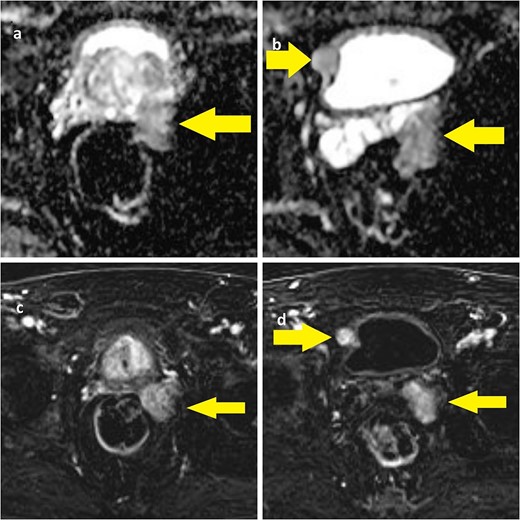

This is a case report of a 65-year-old man with congenital neurofibromatosis type 2 (NF-2) and acoustic neurinoma. The patient came to our outpatient office complaining of predominant voiding LUTS, namely straining and incomplete bladder emptying. Four months before, patients reported a first aid access due to acute urinary retention, requiring bladder indwelling catheterization, anti-inflammatory drugs, and alfa-blockers therapy (silodosin). The International Prostate Symptom Score was 11, and the patient was mostly dissatisfied with his quality of life related to the urinary condition. A digital rectal examination revealed a prostate with a fibro-elastic consistency, well-defined limits, and no apparent palpable mass. The prostate-specific antigen was within the normal range (2.07 ng/ml), with normal renal function and urinalysis. Uroflowmetry demonstrated an arc-shaped curve with a Qmax of 8.5 ml/s, and the postvoid residual was significant (156 ml). The vesical ultrasound imaging showed a 19-mm wide nodular image adjacent to the right bladder wall. The prostate volume was 74 cc with a third lobe. The patient subsequently underwent pelvic MRI, which showed a bulging mass measuring 34 × 29 × 40 mm located in the left seminal vesicle and the presence of a nodular mass measuring 12 mm in the left prostate lobe with a Prostate Imaging Reporting And Data System (PIRADS) score 4 and a well-delineated nodular mass measuring 19 mm near the right bladder wall (Fig. 1).

(a) ADC-weighted MRI showing left prostate lobe and left seminal vesicle lesion; (b) T1-weighted MRI showing left seminal vesicle and right paravesical lesion; (c, d) T1-weighted MRI with same lesions.